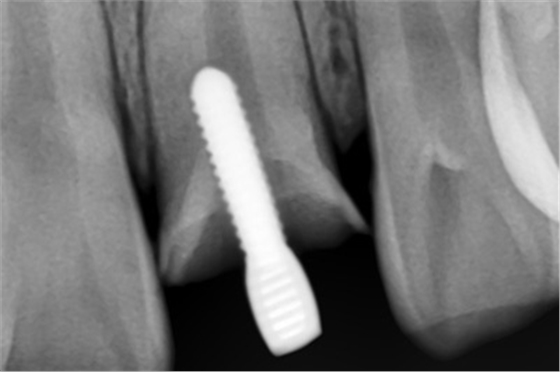

患者外院螺紋樁核加樹脂冠

X線片顯示螺紋釘出根管壁

MTA修補(bǔ)后的X片